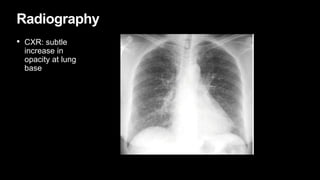

Radiography

• CXR: subtle

increase in

opacity at lung

base

Radiography • CXR: subtle increasein opacity at lung base